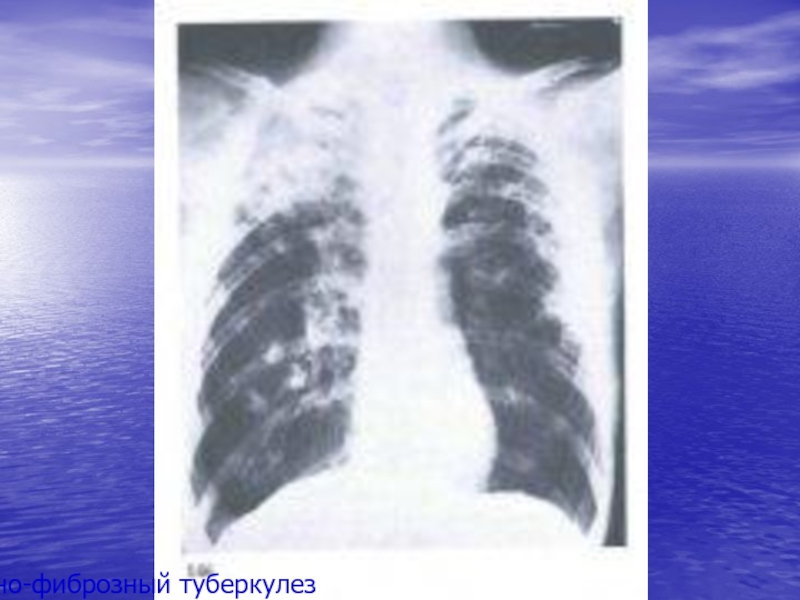

Понимание кавернозного туберкулеза почки

Раздел: Мудрость в деталях